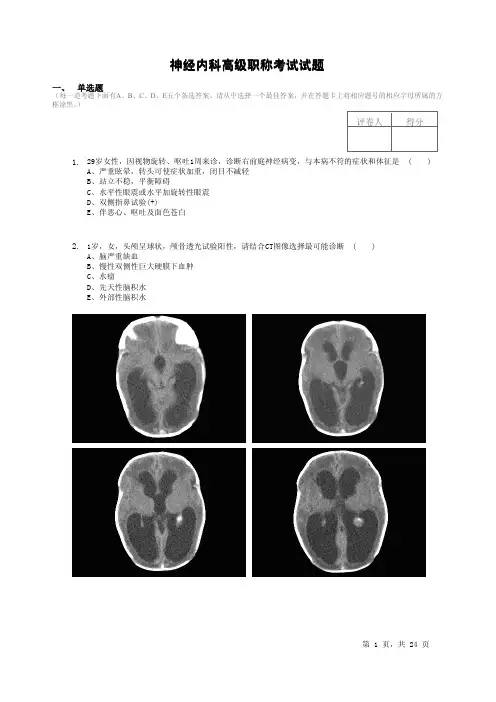

)评卷人得分29岁女性,因视物旋转、呕吐1周来诊,诊断右前庭神经病变,与本病不符的症状和体征是()A、严重眩晕,转头可使症状加重,闭目不减轻B、站立不稳,平衡障碍C、水平性眼震或水平加旋转性眼震D、双侧指鼻试验(+)E、伴恶心、呕吐及面色苍白1.1岁,女,头颅呈球状,颅骨透光试验阳性,请结合CT图像选择最可能诊断()A、脑严重缺血B、慢性双侧性巨大硬膜下血肿C、水瘤D、先天性脑积水E、外部性脑积水2.脑出血后显示典型CT图像和时间为()3.A、病后即示高密度病灶B、病后24~48h示高密度病灶C、病后即示低密度病灶D、病后24~48h示低密度病灶E、病后2~3周示高密度病灶脑卒中最重要的和独立的危险因素是()4.A、高血压B、心脏病C、TIA和脑卒中史D、高脂血症E、糖尿病多发性硬化的下列哪项辅助检查表述是错误的()5.A、急性期脑脊液细胞数显著增多B、脑脊液CSF-IgG指数增高C、脑脊液出现寡克隆带D、视觉及脑干听觉诱发电位可出现异常E、MRIT 像可见侧脑室周围白质散在高信号病灶在Shy-Drager综合征的早期常常有阳痿,原因是()6.A、弥漫性动脉粥样硬化B、锥体束病变C、栓塞性疾病D、自主神经功能不全E、糖尿病下列哪项不是小脑扁桃体下疝的主要临床表现()7.A、延髓受压症B、上颈髓受压症状C、颅高压增高症D、继发脊髓空洞症E、偏盲偏头痛的等位发作的表现哪个不符合()8.A、周期性瘫痪B、消化系统表现C、眩晕发作D、其他症状与头痛交替出现E、无头痛蛛网膜下隙出血恢复期患者,因近2个月头痛逐渐加重并频繁的喷射性呕吐入院就诊。